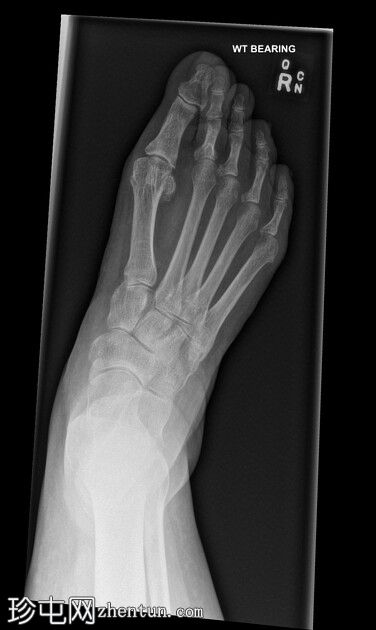

X线片

正位片

第二趾交叉畸形,跖趾关节伸展,足趾内旋,压在相邻拇趾背侧。

第二趾内旋,压在拇趾上。患者有长期穿高跟鞋的病史。